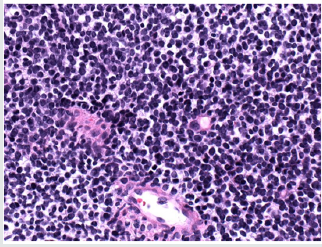

Young male patient complained about soft palate growth. The oral examination showed a non-tender ulcerated mass with an irregular shape and a size of less than 2 cm on the midline of the soft palate (Figure 1). The medical and social history of the patient were unremarkable. A few weeks before the appointment, the palatal lesion was felt by the patient. Based on the clinical features, the working diagnosis was a soft tissue oral malignancy, and a biopsy was scheduled. Histology was consistent with small round cell tumor and a large number of immunohistochemistry stains were scheduled for final diagnosis (Table 1 & Figure 2). Depending on the positivity of Myogenin and Vimentin, the final diagnosis was soft palate embryonic rhabdomyosarcoma. Additional imaging analysis did not reveal any other locations of involvement. The treatment plan consisted of a combination of ifosfamide, vincristine and actinomycin chemotherapy together with 28 radiotherapies (total 5040cGy). The patient had a complete remission of the disease, and no surgery was scheduled. The patient is disease-free one year after initial diagnosis (Figure 3).

Rhabdomyosarcoma is a very rare and highly aggressive malignancy that usually affects children and rarely young adolescents [10]. The prognosis is largely dependent on the stage of the tumor. Diagnosis is a challenge. The clinical signs are nonspecific. Histological image is common in a number of malignant tumors grouped together as “small round (blue) cell tumors,” but each has a completely different prognosis and requires a different therapeutic strategy (Table 1). Accurate diagnosis is largely dependent on immunobiological biomarkers. Rhabdomyosarcomas express Myogenin and MyoD1, which are myogenic transcriptional regulatory proteins identified during skeletal muscle differentiation 1. Early and accurate diagnosis is important as it may make the disease manageable. In a pediatric stage 1 group of patients 7, favorable prognosis was observed. There are only limited case reports in adolescent and postadolescent patients and reported variable treatment strategies cannot support accurate prognosis. Treatment includes traditional surgery, chemotherapy (actinomycin D, doxorubicin, ifosfamide, cyclophosphamide, etoposide, or vincristine) and radiotherapy [11]. Our patient was treated with a mixture of chemotherapy and radiotherapy that fully controlled the disease. So far, he has performed excellently. Treatment sequlae, especially in children, are numerous, including dental abnormalities, hypoplastic jaw bones, trism and hyposalivation / xerostomia, and can have a serious impact on patient quality of life [11].